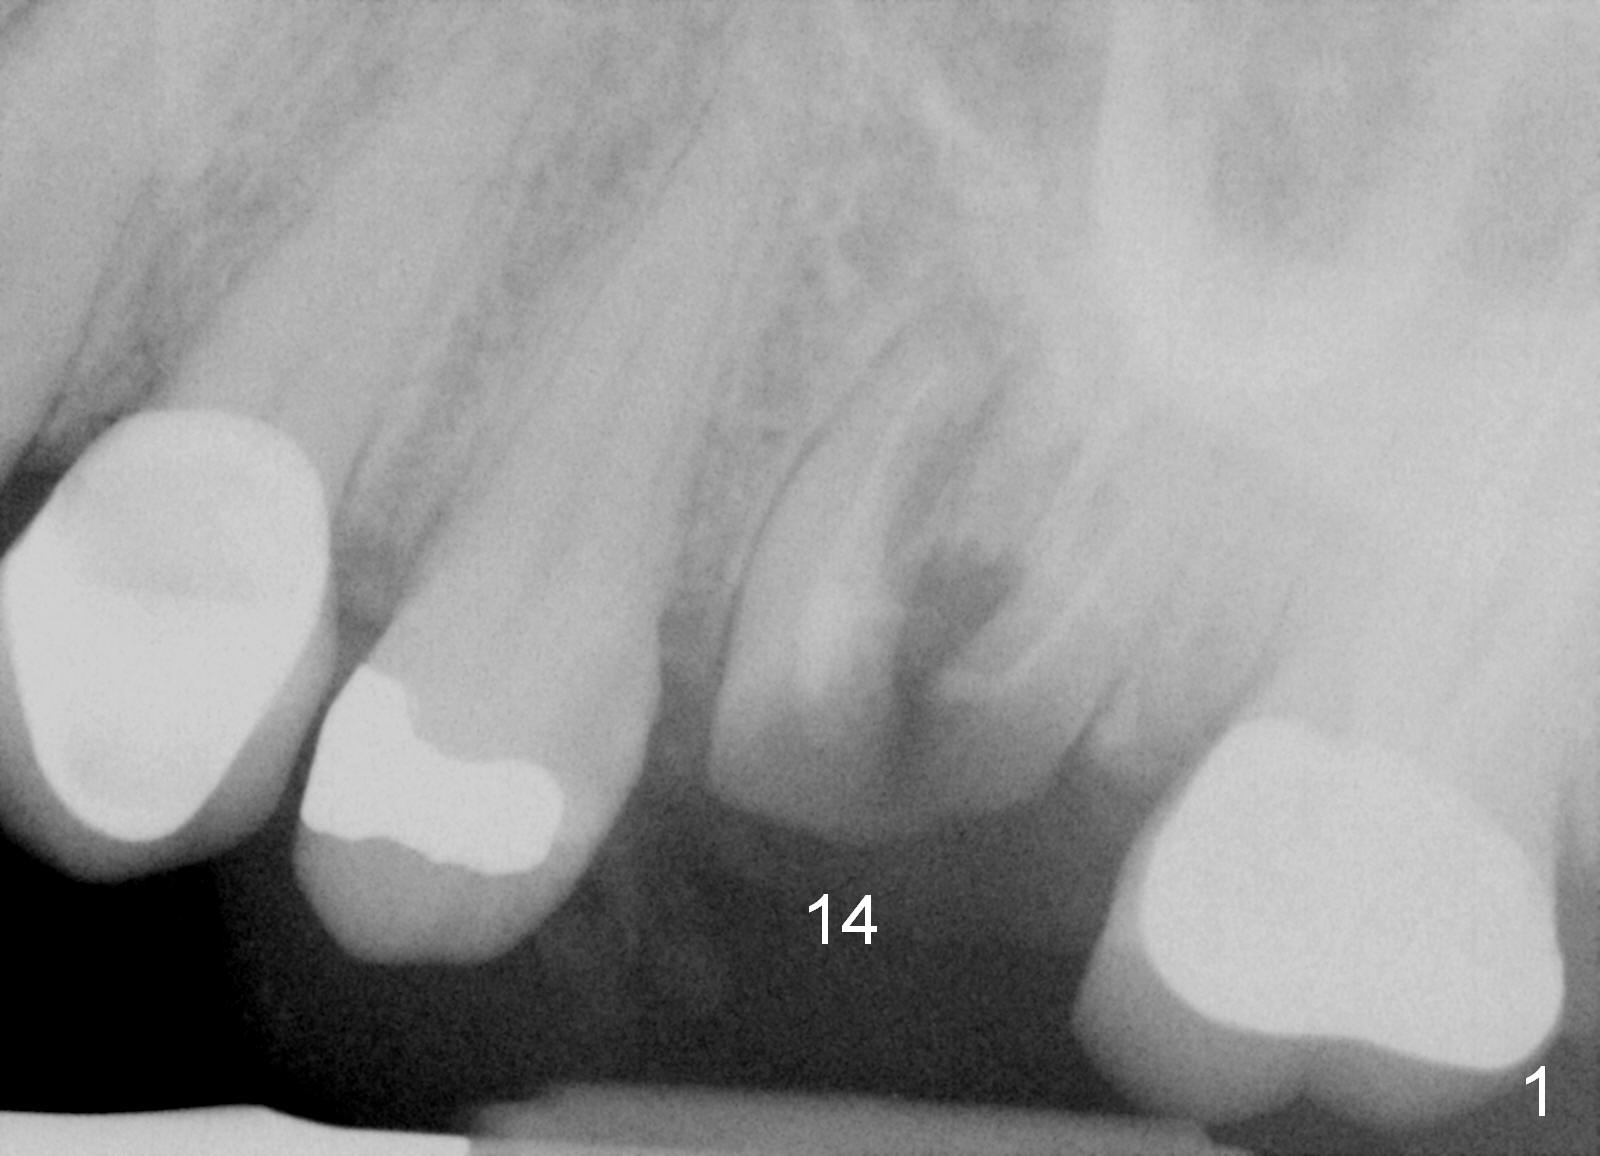

A 58-year-old white woman is afraid of dentistry (Fig1). Two years post extraction of the tooth #14, the bone height reduces by 4 mm (compare Fig.2,3).